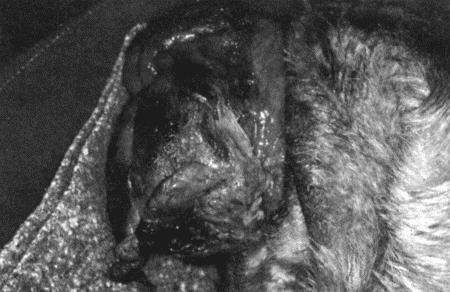

Вагинальная эндоскопия

Прекращение секреции эстрадиола фолликулами и переход их к секреции прогестерона приводят к снижению как отечности, так и васкуляризации слизистых оболочек, что сопровождается выраженным изменением характера вагинальных выделений, выявляемым с помощью вагинальной эндоскопии. На стадии проэструса слизистая оболочка становится более выпуклой и отечной, затем наблюдается ее уменьшение; по мере приближения овуляторного пика слизистая сжимается и бледнеет, в некоторых случаях становясь практически белой (фиг. 1.1). Перечисленные изменения свидетельствуют о приближении стадии, характеризующейся постепенным повышением концентрации прогестерона перед овуляцией и последующим наступлением фертильного периода. Эти изменения легко узнать, имея даже небольшую практику (фиг. 1.3), кроме того, они настолько воспроизводимы, что по набору признаков их можно оценивать полуколичественно. Вагинальная эндоскопия весьма полезна в определении оптимальных сроков вязки. По окончании фертильного периода, т. е. в начале метэструса — слизистая оболочка влагалища бледнеет и истончается, складки становятся закругленными — и что, вероятно, является наиболее характерным признаком, — слизистая в переднем отделе влагалища выглядит раздраженной и при прикосновении быстро сжимается, образуя розетку.

Фиг. 1.3.

Эндоскопическое исследование слизистой влагалища. Динамика изменений на протяжении цикла: (а) проэтрус — розовая окраска и отечность; (b) начало эструса — слизистая бледнеет, отек начинает уменьшаться (обычно перед пиком ЛГ); (c) середина эструса — слизистая бледная, уменьшение отека (сморщивание) явно выражено, что соответствует середине фертильного периода; (d) начало метэструса — видны закругленные складки, при прикосновении слизистая смыкается, образуя розетку (е) (см. Приложение)